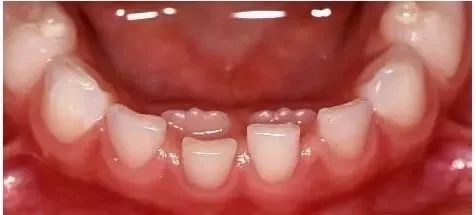

图注:下前牙一般早于上前牙替换

大多数孩子是从下门牙开始换,但每个孩子的换牙顺序都不是百分百固定的,“不走寻常路”的孩子也不少。

比如有些孩子是先从上门牙开始换,只要牙齿松动度正常,没有严重的龋坏或外伤,也属于正常现象。